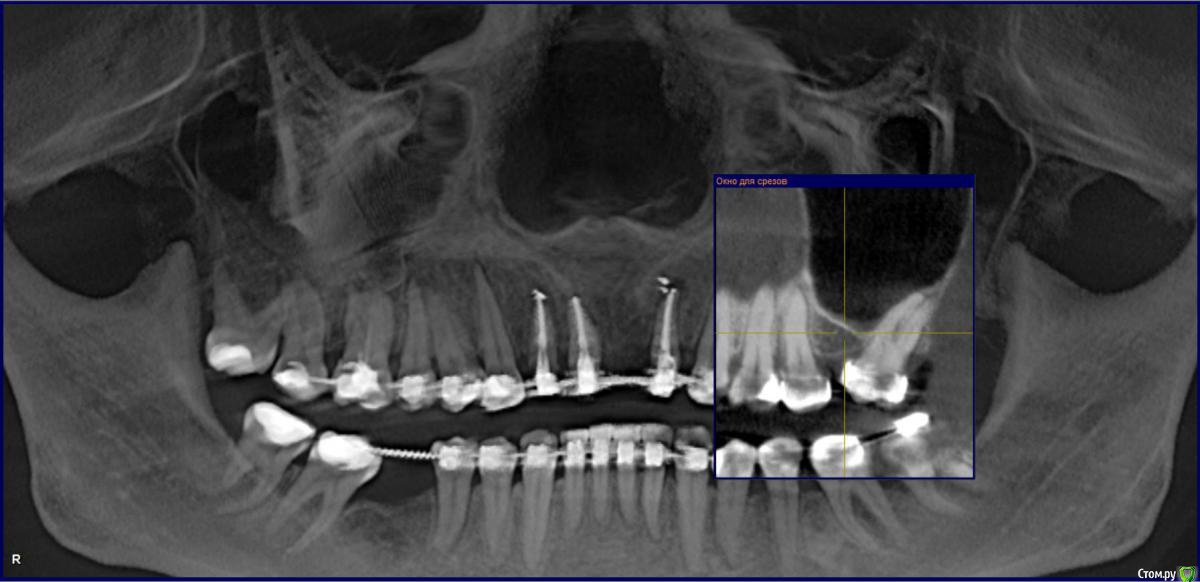

Kazankov.Egor Опубликовано 15 апреля, 2017 Поделиться Опубликовано 15 апреля, 2017 (изменено) Здравствуйте, нужен совет, прибыла пациентка из другого города на долечивание, по первоначальному плану планировалась мезиализация 27, предпринималась ее попытка, но был получен только наклон. В прикрепленном орто состояние на данный момент. У кого-то был успешный опыт мезиализации в таком случае? Как ведет себя кость в области синуса/корней? Изменено 15 апреля, 2017 пользователем Kazankov.Egor Ссылка на комментарий

Opdihatop Опубликовано 15 апреля, 2017 Поделиться Опубликовано 15 апреля, 2017 Все возможно, но довольно долго. Если не идет на прямой дуге (только полностью заполняющей паз) тяните за микроимплант и высоко припаянный крючок. Тогда наклона не будет. Дно синуса перемещается вместе с зубом. Ссылка на комментарий

АнтонТЛТ Опубликовано 15 апреля, 2017 Поделиться Опубликовано 15 апреля, 2017 Кортикотомия дна пазухи мезиальнее зуба поспособствует корпусному перемещению. Хотя правильнее зуб дистализировать и поставить имплантат с синус-лифтингом. 1 Ссылка на комментарий